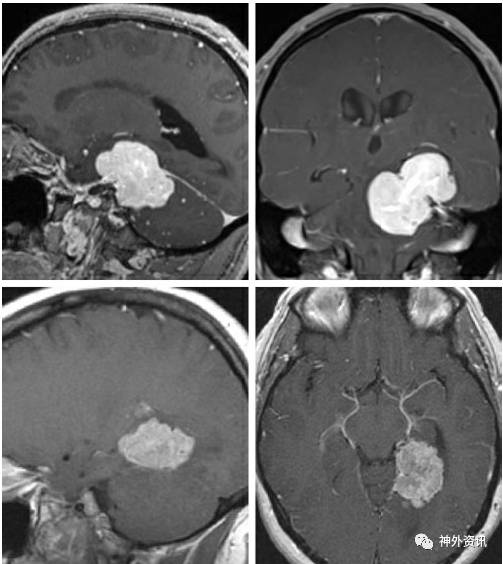

Large Midline Pineal Region Pineoblastoma-The Paramedian Supracerebellar Approach

图1. 相对于中线入路,旁正中小脑上入路有许多优势: 1) 颅骨切开术多数不会威胁到优势侧(右侧)横窦和窦汇,更微创;2) 只经过一侧小脑半球进行操作;3) 通常情况小脑蚓部桥静脉受到保护;4) 经小脑外侧的视线斜度更小,为显露肿瘤下极提供较清晰的视线。再次手术可以通过对侧的小脑上入路完成。旁正中或者中线入路可以显露第三脑室后部肿瘤(下图)。

图2. 松果体区(左图)及中脑后外侧(右图)大型病变可以很容易通过小脑上入路显露。

MR图片可以明确深静脉结构(Galen静脉、基底静脉、大脑内静脉和直窦) 和手术途径及肿瘤之间关系的关键信息。偶尔,后部丘脑和小脑蚓部肿瘤类似松果体区占位,逐渐向后推移间脑引流静脉,这种情况是小脑上入路的潜在禁忌。另外,肿瘤对其周围神经结构浸润的程度 (如中脑、丘脑) 必须在手术之前明确。